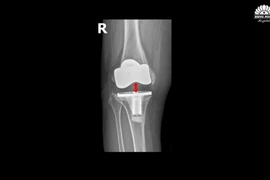

Chữa thành công biến chứng khớp gối nhân tạo hiếm gặp sau 5 năm

Thay thế khớp mới bằng kỹ thuật thay khớp gối gióng trục động học, không cắt gân cơ với đường mổ nhỏ, ít xâm lấn, giúp bệnh nhân đi lại sau 1-2 ngày.